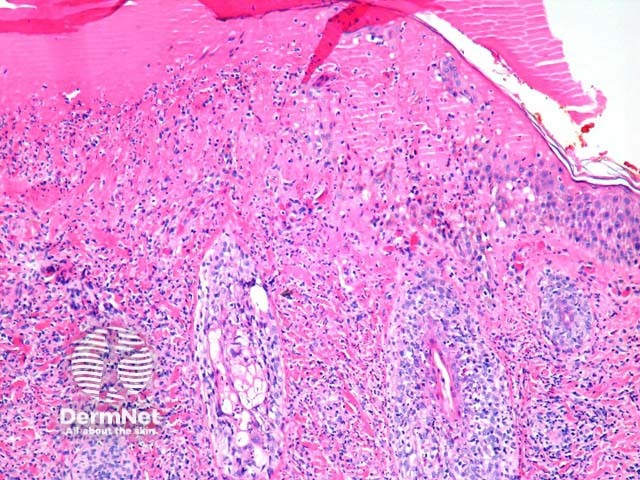

In hydroa vacciniforme, sections show epidermal spongiosis, vesiculation and necrosis overlying a dense dermal infiltrate (figure 1). The necrosis may be confluent (figures 2, 3) and infiltrated by a mixture of acute and chronic inflammatory cells. In older lesions there may be scarring.

Figure 1